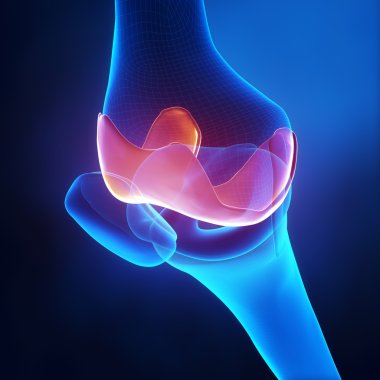

diz, anatomi, kemik

RenderkişiİnsanKadınerkekTıbbiAdamciltParmaklarKemikkolgövdebiyolojiOmuzGöğüsAcıDizkafatasıomurgaEklemKaburgaKalçaİskeletanatomiomurilikRADIUSx ışınıAğrıkadınlarKafesgörevleriçene kemiğiGöğüs kemiğiskapulaLeğen kemiğikarpalsakrumTibiaUyluk kemiğifibulaKöprücük kemiğipazı kemiğidirsek kemiğibasdiz kapağıkemiklerischiumdziewczynkiBenzer İçerikler